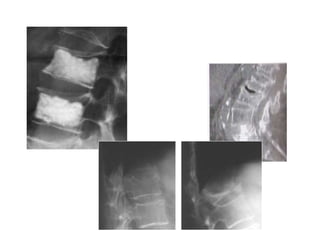

Vertebra Plana

Pre Post 1y 3y

Kyphoplasty

It is important to fill the anterior 2/3–3/4

of the vertebral body

Cement should reach or cross the midline to

reinforce both halves of the vertebra (white

arrows)

A Unipedicular PV

shows distribution of cement into

both halves of the vertebra

Inflatable ballon in the midline of the fractured body

Tip of the guide pin over the center of the vertebral body